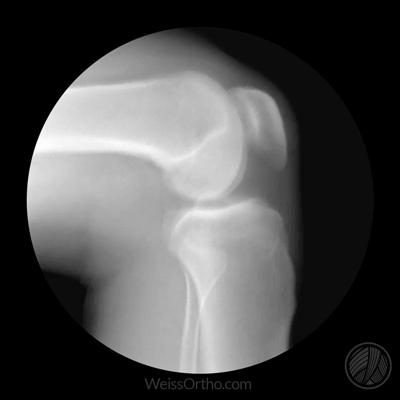

髌骨骨折经历数月,无论是保守或者是手术治疗,应该骨折已经愈合了,此时如果出现关节的疼痛,应该首先做的是去医院进行膝关节x线检查,进行复查,明确骨折是否彻底愈合了,是否有明显的骨质疏松,如果是髌骨的保守治疗,患者关节内没有金属结构的话,可以进行核磁检查,明确关节内的软骨是否存在着问题。

如果发生了髌骨彻底的骨折,x线上我们能看到的只是骨头的折断,但是实际上,髌骨后方是有一层非常重要的结构→关节软骨也跟随着骨头的折断而折断了!

对于这种情况可能诱发的膝关节疼痛,如果是保守治疗的患者,没有金属内固定,建议进行核磁检查观察软骨的情况,而如果有内固定的朋友,建议首先复查膝关节的x线片子,如果骨折已经愈合了,建议取出内固定以后进行膝关节的核磁检查,明确关节腔软骨的情况。